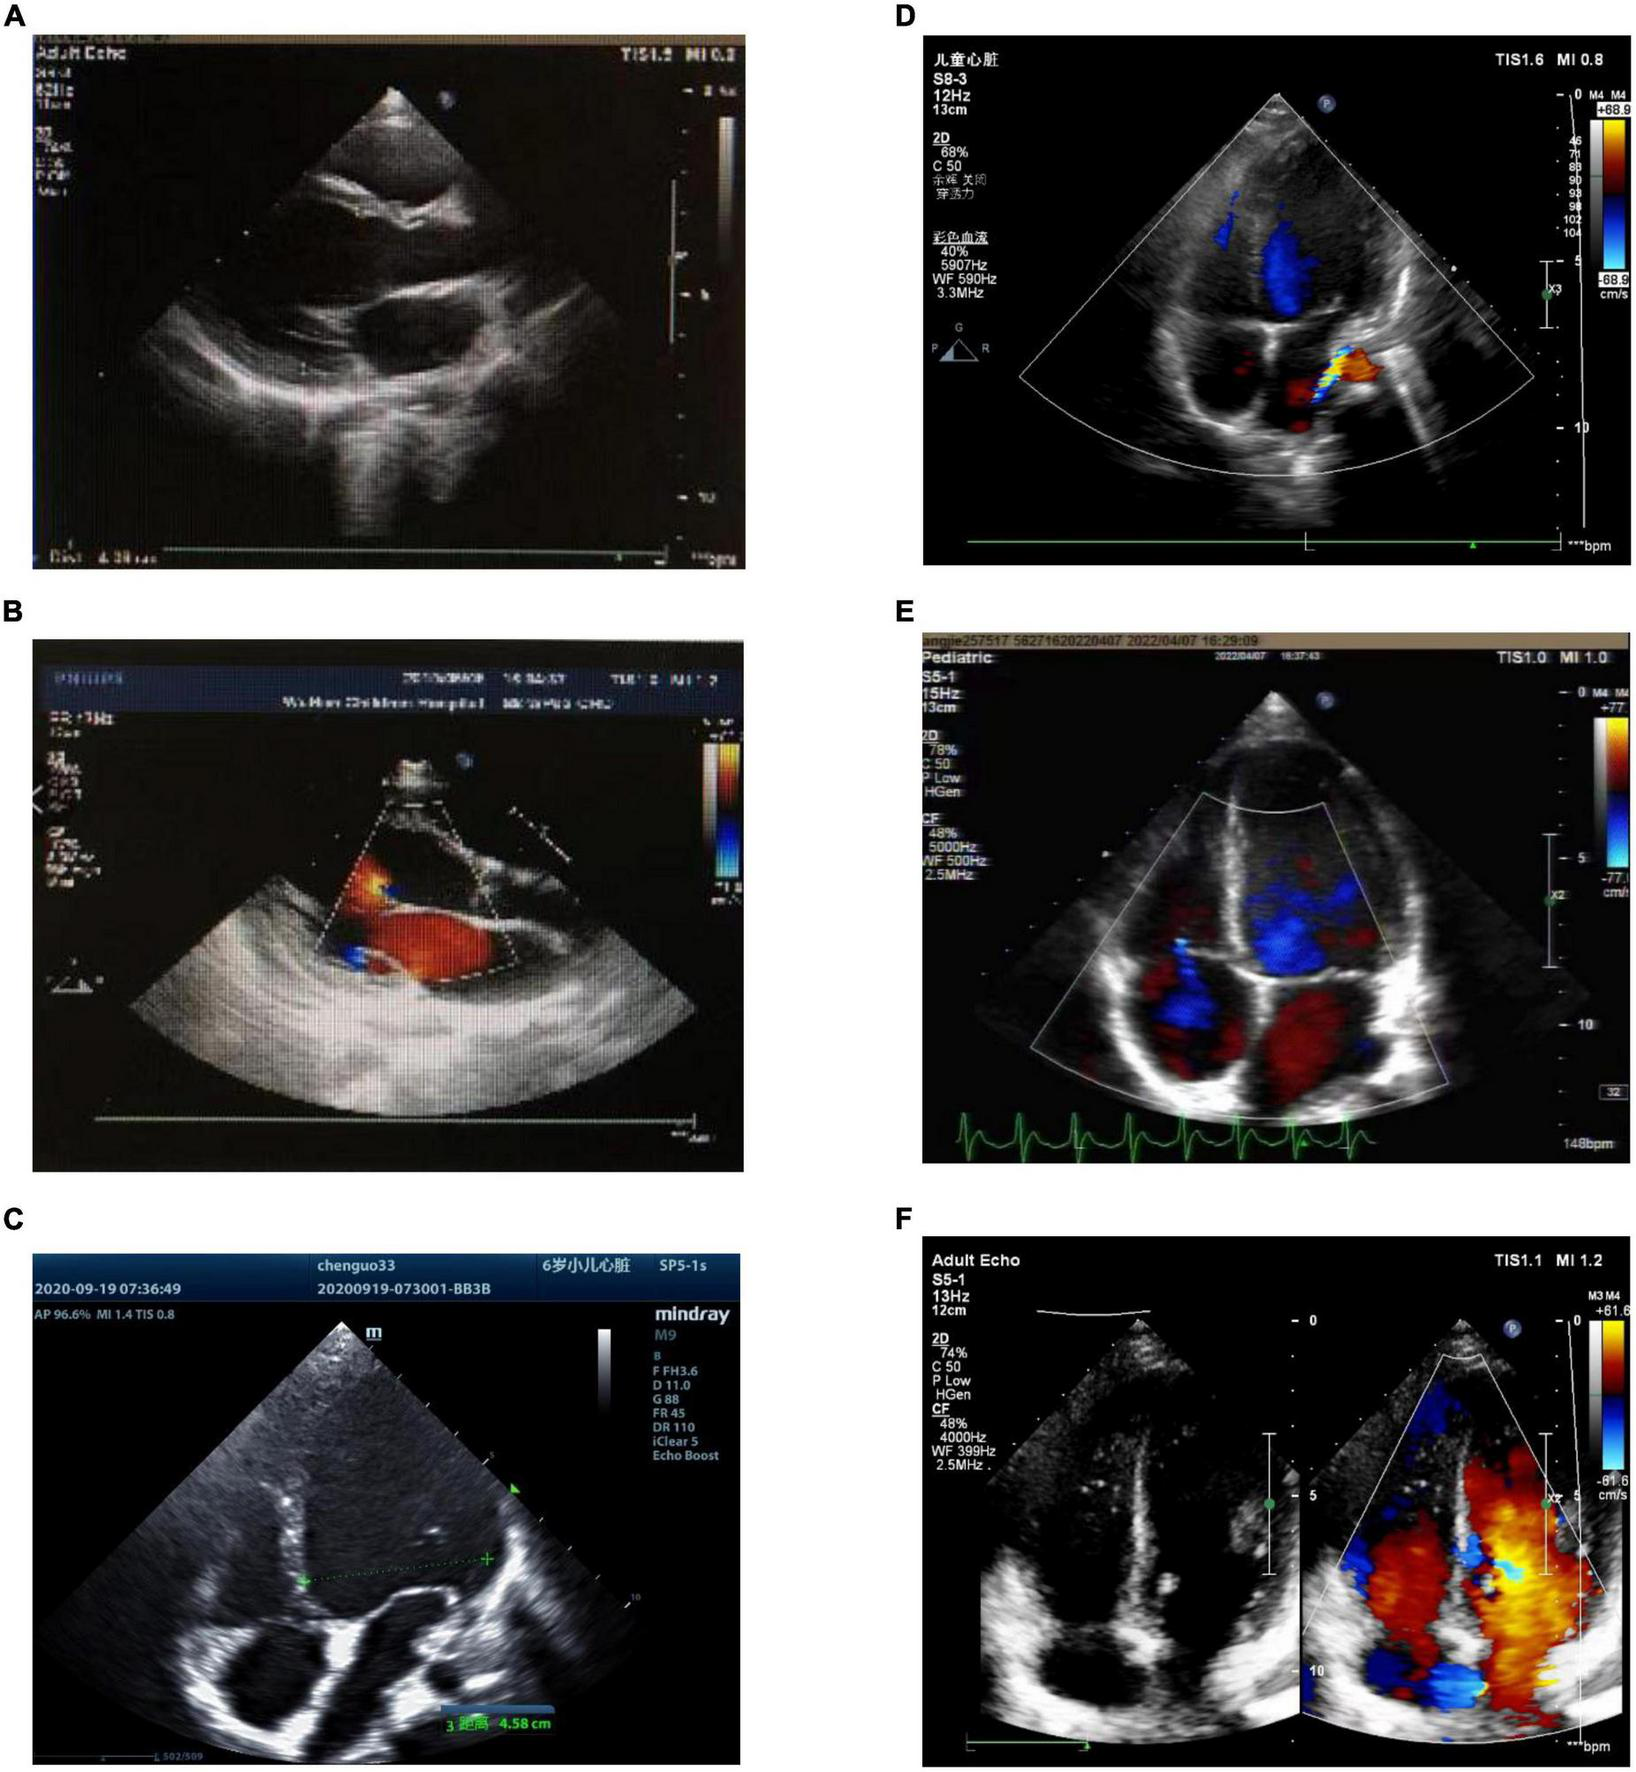

After the operation, all three children recovered sinus rhythm (Figure 1). Follow-up from 1°month to 1.5 years showed no recurrence of AT, and heart size and ejection fraction gradually recovered (Figures 1, 4 and Table 1).

FIGURE 4

Preoperative and postoperative echocardiography of atrial tachycardia (AT) from the atrial appendage. (A) Case 1: preoperative echocardiography. Left ventricular end-diastolic diameter (LVEDD) 40 mm, left ventricular ejection fraction (LVEF) = 42%. (B) Case 1: echocardiography 1°month after radiofrequency catheter ablation (RFCA). LVEDD 37 mm, LVEF = 53%. (C) Case 2: preoperative echocardiography. LVEDD 45.8 mm, LVEF = 29%. (D) Case 2: echocardiography 1°month after LAA resection. LVEDD 37 mm, LVEF = 46%. (E) Case 3: the left picture shows preoperative echocardiography. LVEDD 45 mm, LVEF = 45%. (F) Case 3: echocardiography 1°month after RAA resection. LVEDD 42 mm, LVEF = 56%. LVEDD, left ventricular end-diastolic diameter; LVEF, left ventricular ejection fraction; RFCA, radiofrequency catheter ablation; LAA, left atrial appendage; RAA, right atrial appendage.